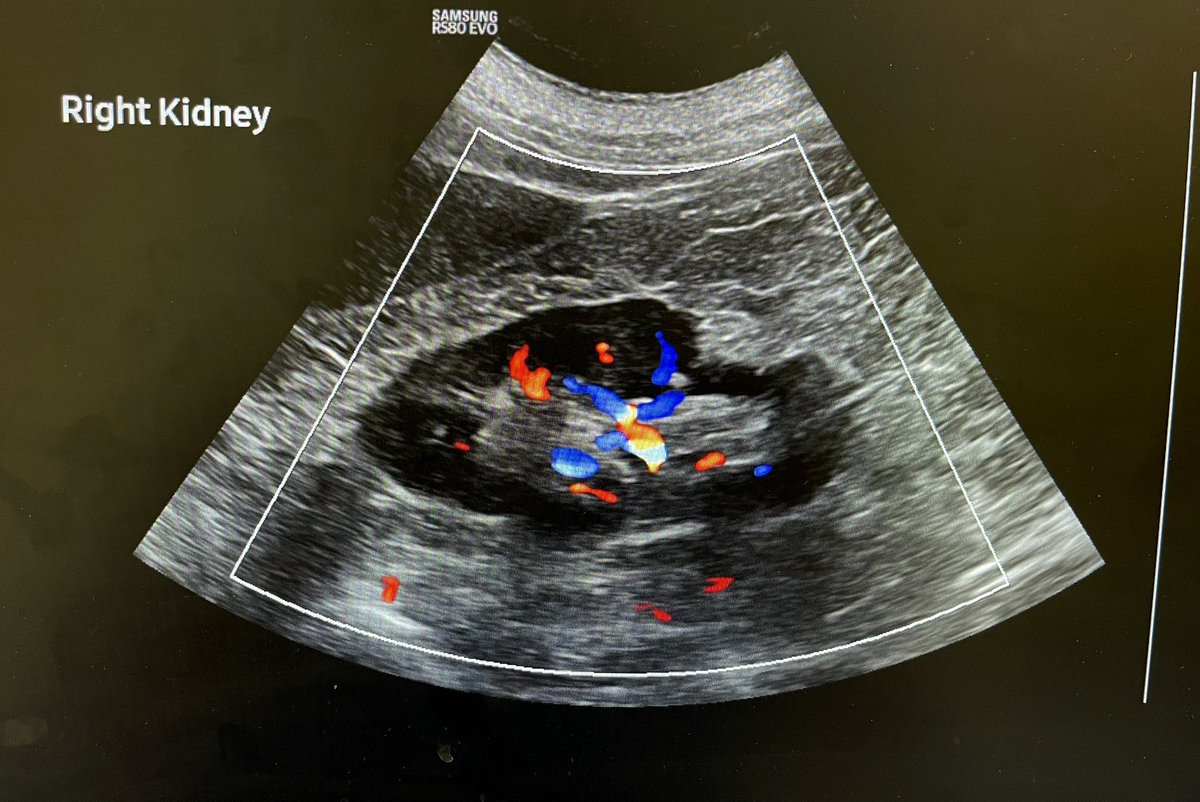

54F with right flank pain and haematuria. Solid heterogeneous right renal mass with vascularity. ? Renal cell carcinoma. @Rad_Munagi @AjuboDaso